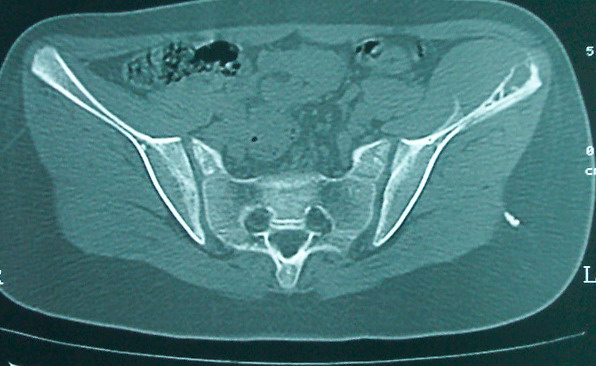

女 13岁 4月前有臀部肌肉注射史 3月前发热 最高体温38.5 2月前出现左髂骨疼痛 不剧烈能忍受 发热时高时低 按感冒治疗无好转 近日左髂骨疼痛加重 一星期前wbc 12.2 今日wbc9.5

左侧髂骨溶骨性骨质破坏,骨皮质侵蚀,灶周可见软组织肿块,支持考虑骨肉瘤可能性大。

髓腔起源,弥漫性溶骨性骨质破坏并软组织肿块,膨胀不明显,无显著钙化及瘤骨,有骨膜反应,结合年龄考虑恶性,尤文氏肉瘤可能性大。

鉴别:尤文氏肉瘤>毛细血管扩张型骨肉瘤>骨原发淋巴瘤>朗格罕氏细胞增生症>软黏纤>慢性骨髓炎>tb。

左侧髂骨溶骨性骨质破坏,骨皮质侵蚀,灶周可见软组织肿块

支持髂骨低毒性骨髓炎或骨结核:骨质破坏,髂腰肌明显肿胀,非长管状骨部位。

左侧髂骨溶骨性骨质破坏,骨皮质侵蚀,灶周可见骨膜反应及软组织肿块,支持考虑骨肉瘤可能性大。